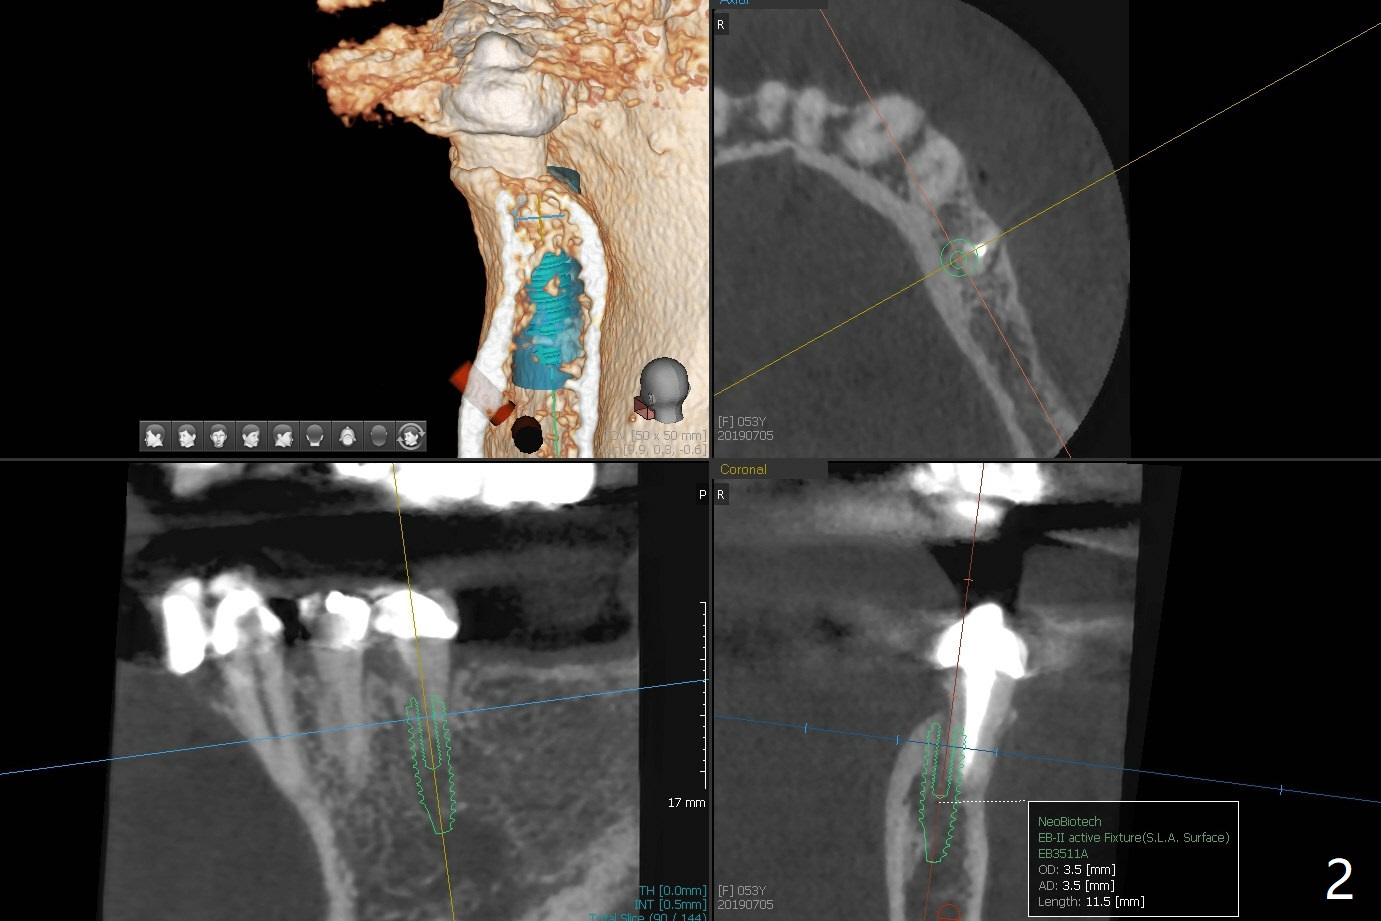

A 53-year-old woman develops an abscess lingual to the tooth #20 before #19 final restoration. Reanalysis of CT taken 5 months earlier shows the thin buccal plate (Fig.1 B). A 3.5x13 mm bone-level/3.5x17 mm tissue-level implant should be lingually placed (Fig.2,3). Socket shield will be performed (Fig.4 *); the lingual cortex removed with Lindamann bur (red) for ~1.6 mm. Initial osteotomy will be conducted in the lingual wall of the socket coronally (Fig.5 white arrow); after penetration, the initial drill will change the trajectory (Fig.6).